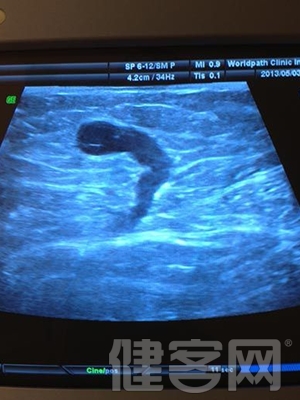

主刀醫生親自做術前超聲檢查定位,是發達國家靜脈曲張治療的常規流程,具有以下的作用:

交通靜脈和小隱靜脈病變往往在外表上不明顯,必須要超聲檢測,但是國內幾乎所有醫院的超聲報告,都缺乏這兩項檢查的描述。因此,容易導致術後復發。

(2)通過彩超定位,可以了解詳細的血流方向和病變發布情況,可以有效減少盲目的切口。

(3)手術醫生親自做術前超聲檢查,可以更有效地對疾病作出判斷,減少並發症。

主刀醫生的手術前彩超檢查,可以使得治療個體化設計,避免無謂的復發和並發症。